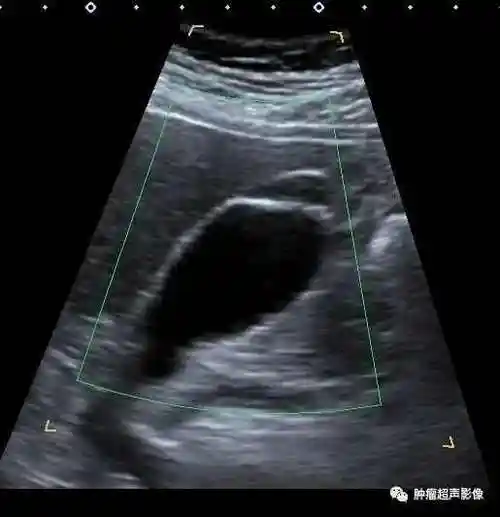

胆囊腺肌症的超声诊断